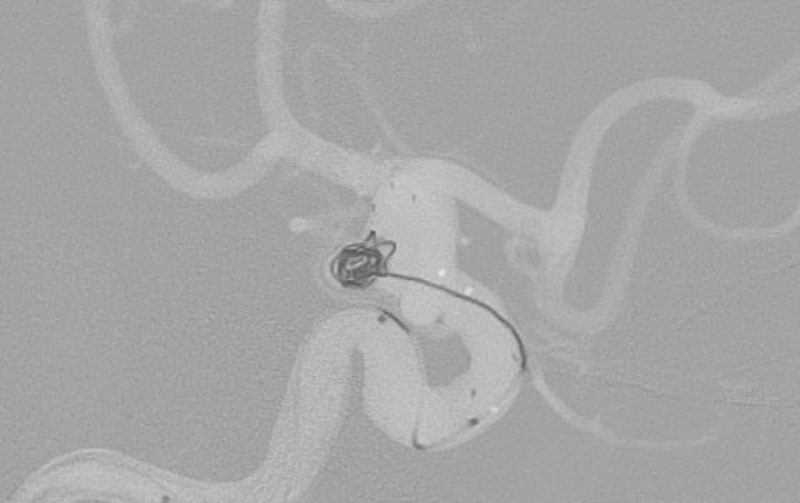

'25年11月

くも膜下出血

右内頚動脈後交通動脈

分岐部動脈瘤破裂

60代

救急外来

No.1593 手術前

No.1593 手術中

No.1593 手術後